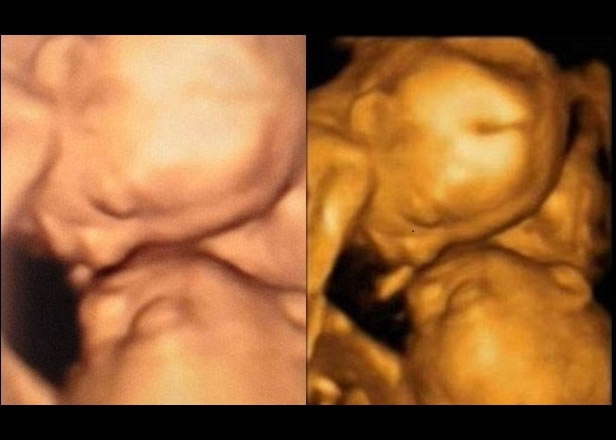

(蜘蛛网报道)美国食品及药物管理局(FDA)日前作出警告,指现时坊间流行、为孕妇腹中婴儿拍摄3D超声波照留念的收费服务,或会有损婴儿健康,称婴儿的组织会在过程中受热,或令他们长出小水泡。FDA指,超声波测试应只用作医学用途,及由执业医护人员负责。

为胎儿照超声波可以帮助医生,判断婴儿的健康、大小及年龄,并了解他是否存在任何缺陷。